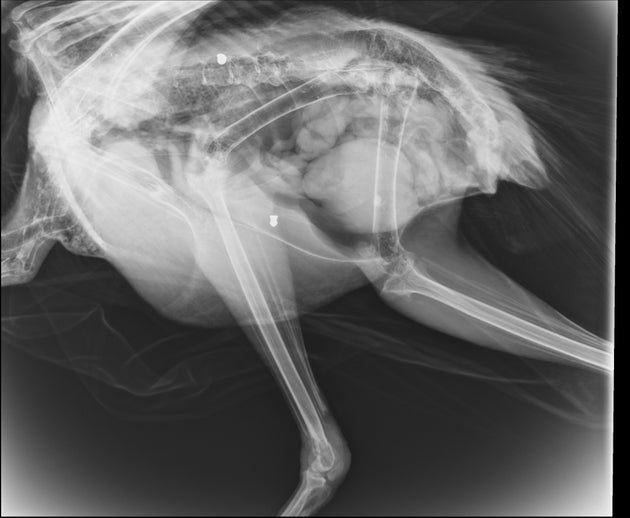

Συγκεκριμένα το πτηνό στάλθηκε στον Σύλλογο μέσω του Μουσείου Φυσικής Ιστορίας Κρήτης από τον αρχαιολογικό χώρο της Κνωσσού, επειδή κούτσαινε εδώ και λίγο καιρό. «Με έκπληξή μας, εμφανίζοντας την ακτινογραφία, είδαμε δυο βολίδες αεροβόλου κι ένα σκάγι μέσα στο σώμα του!», αναφέρει η ανακοίνωση.

Με έκπληξή μας, εμφανίζοντας την ακτινογραφία, είδαμε δυο βολίδες αεροβόλου κι ένα σκάγι μέσα στο σώμα του!

Το ζώο αυτό έχει πυροβοληθεί τρείς φορές, την ίδια ώρα ή διαφορετικές δεν μπορούμε να ξέρουμε, ούτε αν ο δράστης είναι ένας ή δύο ή τρεις, μέσα ή δίπλα σε έναν από τους πιο πολυσύχναστους αρχαιολογικούς χώρους της Κρήτης και της Ελλάδας γενικότερα».